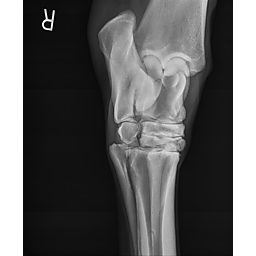

**Tex sells at the Colorado Horse Sale's Best of the West Select Sale on May 30th in Castle Rock, CO - He will complete the riding & handling Sift Exam, baseline veterinary exam, and will sell with 4 total radiographs (DLPMO & Front Foot Lateral)**